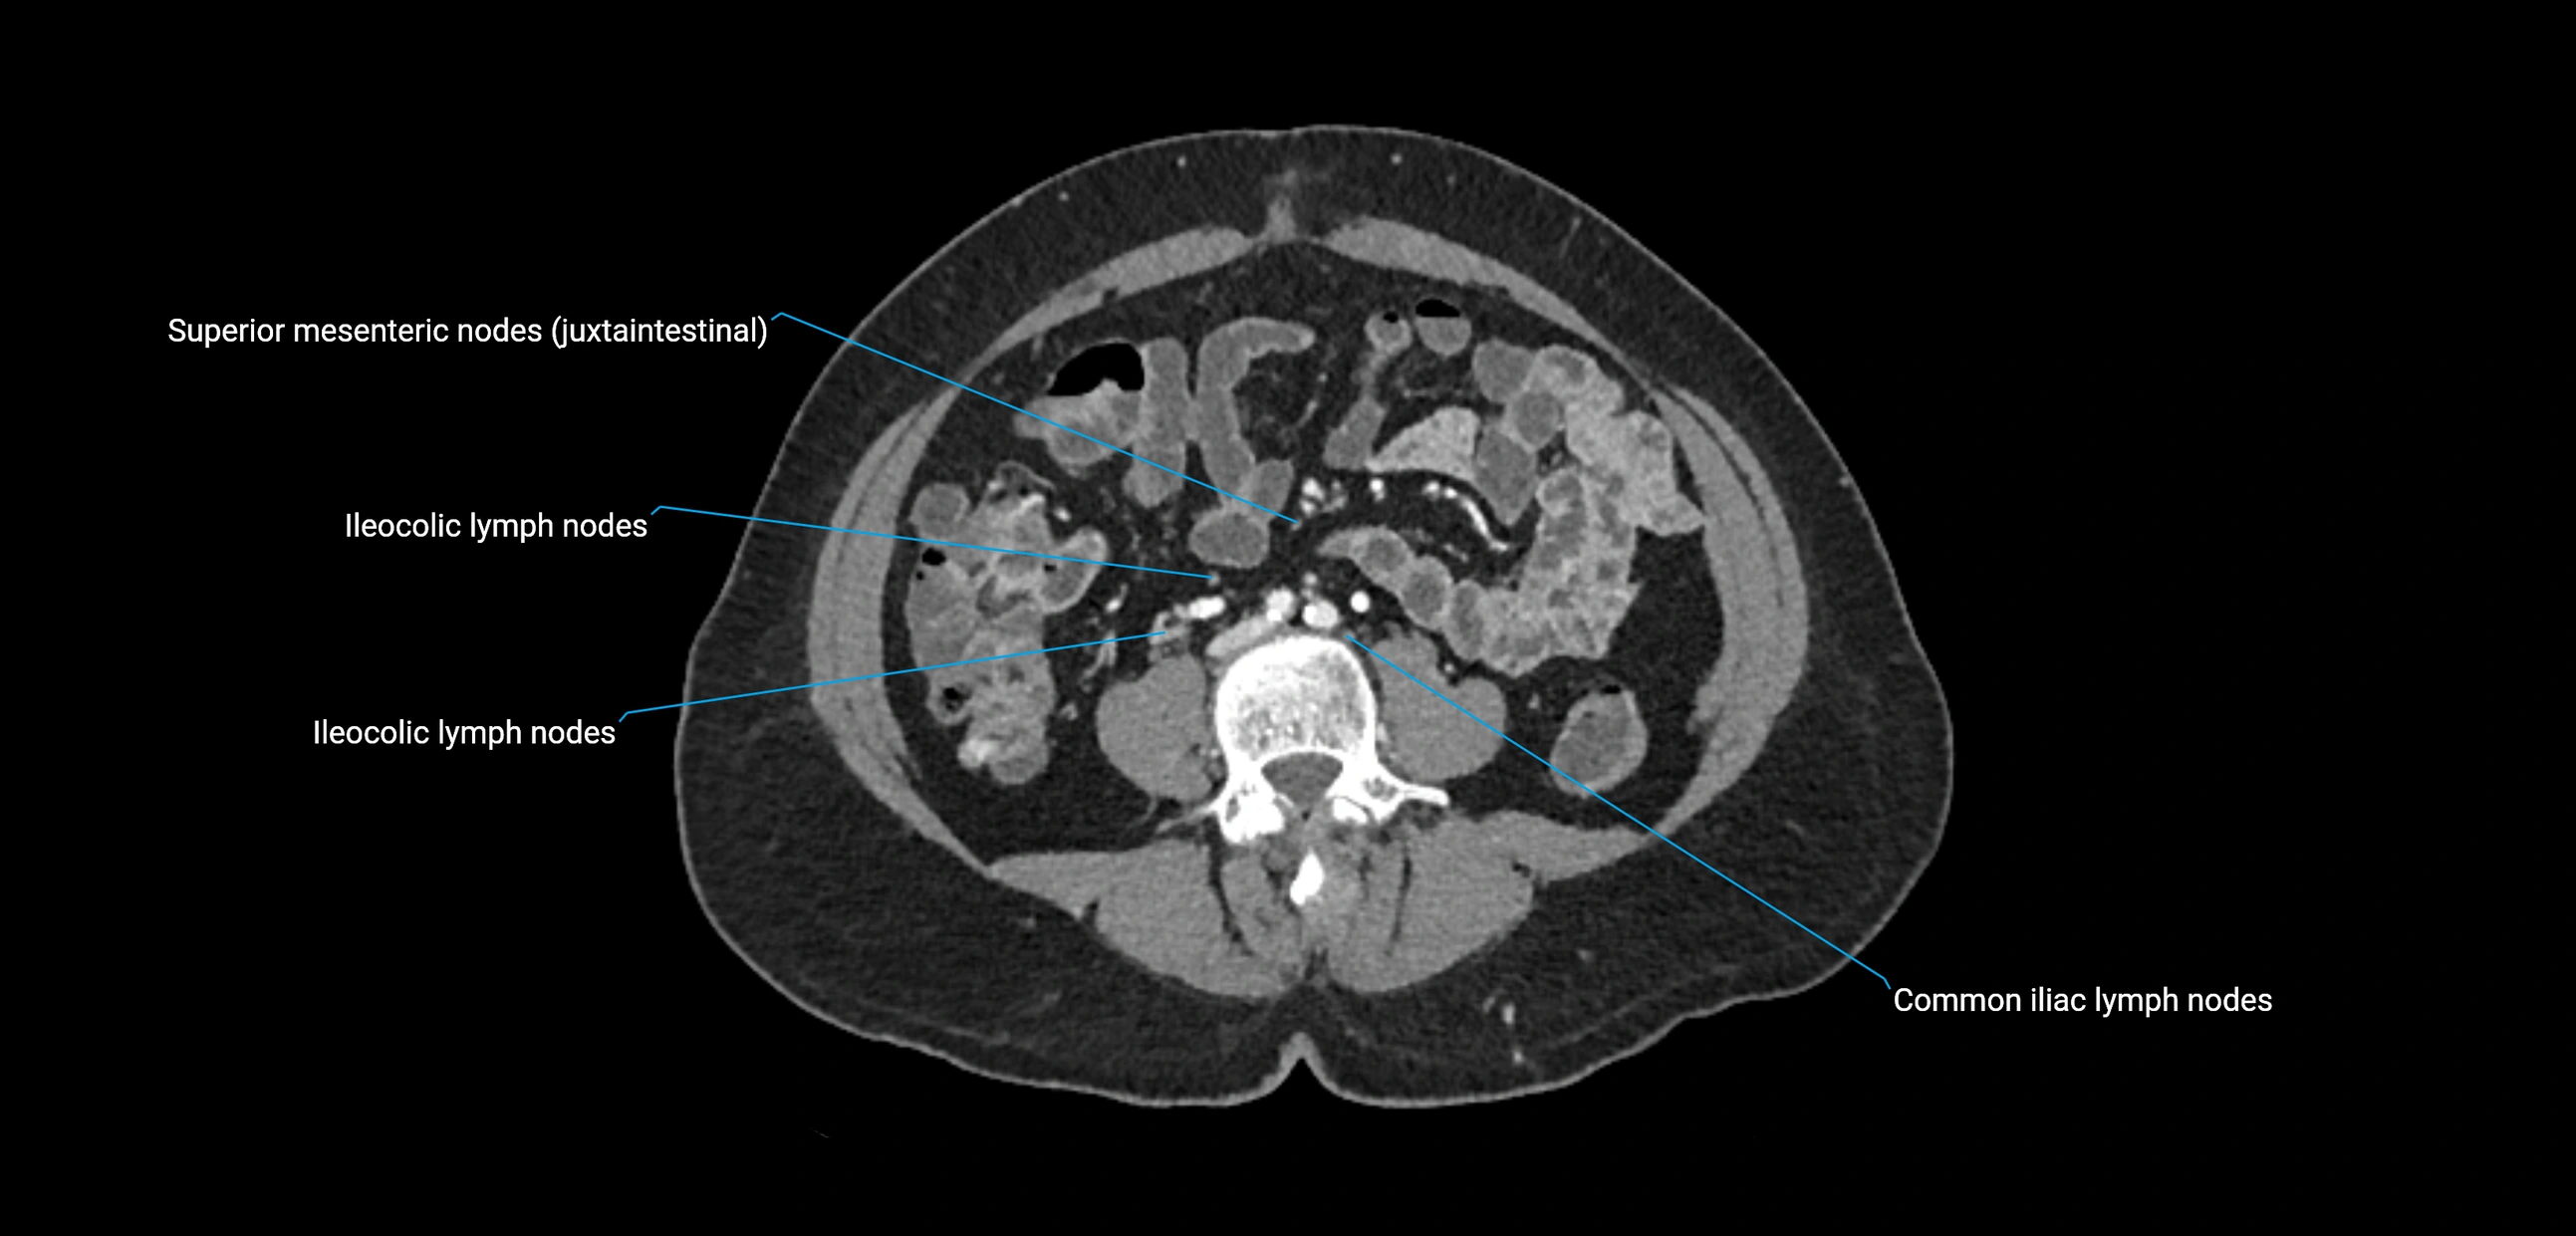

CT image

image